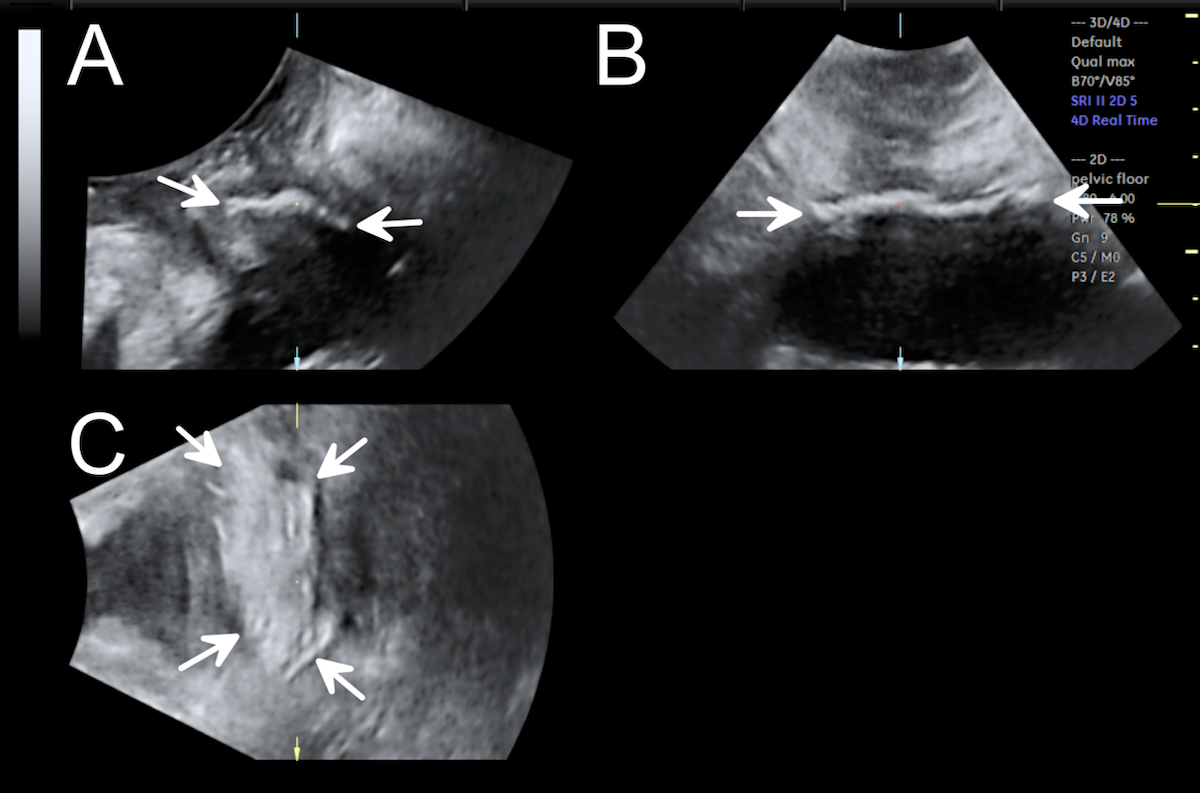

Transperineal ultrasound is well suited for imaging of meshes and slings as these implants are highly echogenic on ultrasound and the technique allows assessment of the functionality of synthetic implants on Valsalva. It helps determine the presence or absence of synthetic implants (Figure 4), assess the number and type of sling or mesh, location, and course in the pelvis. Imaging should be performed in women with complications, such as recurrent urinary tract infections, voiding difficulties, recurrent urinary incontinence or prolapse, implant erosion into adjacent organs or chronic pain. This is especially the case if revision or removal of synthetic implants is contemplated, to help predict likely functional outcomes after removal, to optimize patient counseling and surgical planning (Shek & Dietz 2021).

Figure 4: A transvaginal mesh in the three orthogonal planes on Valsalva maneuver.